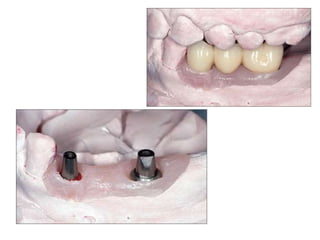

Implants require more precise impressions than crowns and bridges because implants lack a periodontal ligament to compensate for inaccuracies. It is critical to accurately record the three-dimensional position, angulation, and depth of implants to obtain a proper fitting definitive restoration. Making high quality impressions at the implant or abutment level is necessary to successfully fabricate implant prostheses.